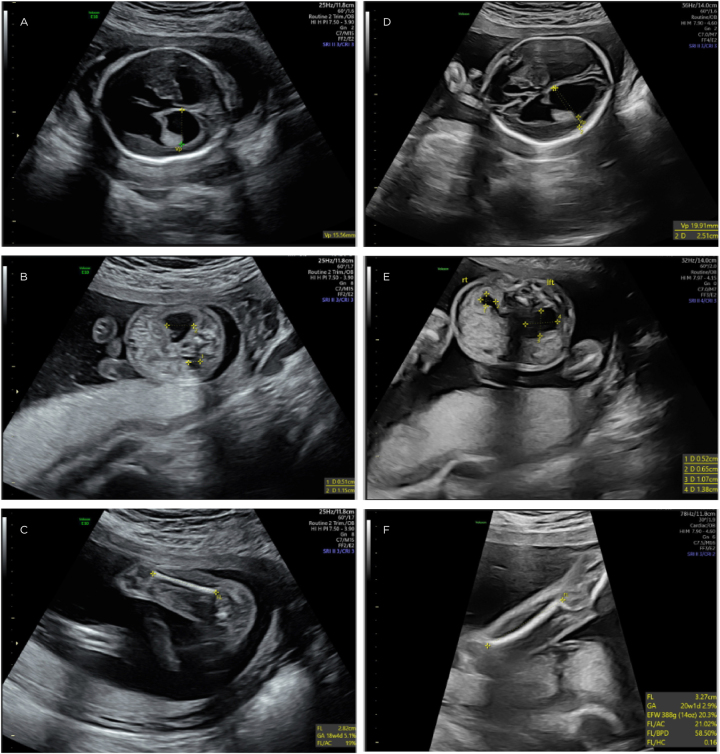

Case presentation: A 35-year-old G1P0 healthy female found at anatomy scan to have multiple fetal anomalies, including severe bilateral ventriculomegaly, renal pyelectasis, and short long bones. Karyotype and microarray were normal. Whole exome sequencing showed the fetus was compound heterozygous for likely pathogenic variants in the ROBO1 gene.